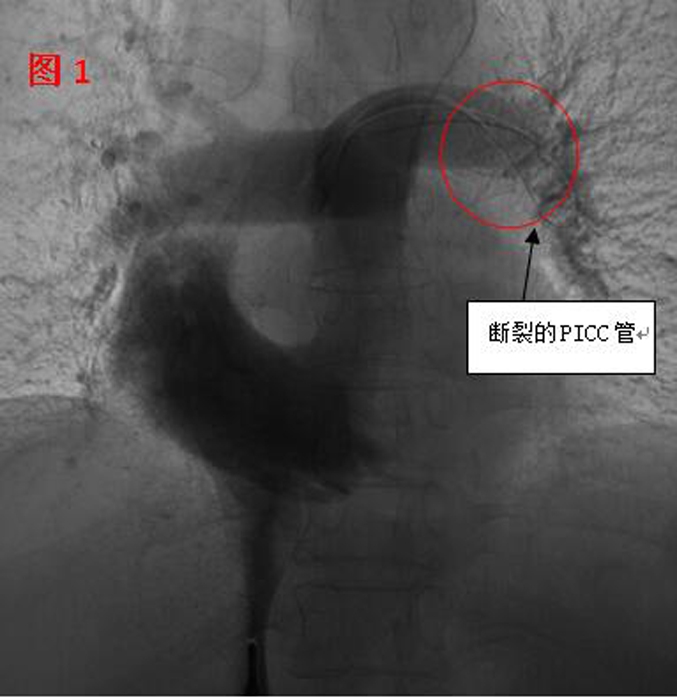

??? 11月2日,在醫(yī)院多個科室的配合下,這臺心臟異物取出術(shù)開始了。血管外科醫(yī)生在手術(shù)時發(fā)現(xiàn),斷裂的PICC管竟完全移位至病人的心室、肺動脈(見圖1),情況十分棘手。術(shù)中應用異物捕捉系統(tǒng)時,由于導管隨心臟跳動和呼吸的影響,擺動巨大,捕捉后導管反復滑脫,且術(shù)中患者心臟稍受刺激就會出現(xiàn)心律失常。